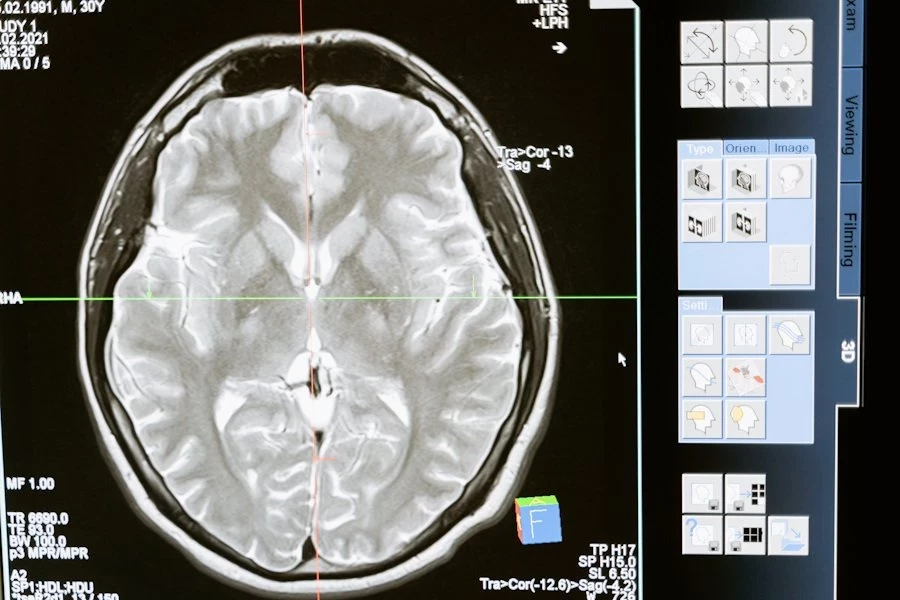

Precision Neuroscience, конкурент Neuralink, проводит клиническое исследование подключив свой нейроинтерфейс к мозгу человека

Precision утверждает, что их технология не потребует проведения открытой операции на головном мозге. В интервью с CNBC в январе соучредитель и генеральный директор компании Майкл Магер объяснил, что хирург сможет имплантировать устройство, сделав маленький разрез в черепе, который будет настолько тонким, что пациентам не придется брить волосы для процедуры.

Минимально инвазивный подход Precision является разумным выбором, поскольку другие конкурирующие компании, такие как Paradromics и Neuralink, разрабатывают системы, которые вводятся непосредственно в ткань мозга.